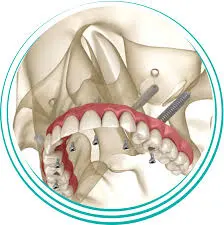

Pterygoid dental implants are anchored at a 45-degree angle into the pterygoid bone in the back of the upper jawbone. This type of implant is typically used when there is insufficient bone volume in the upper jawbone to support traditional dental implants.

Since the pterygoid bone is a strong and dense bone that provides excellent support for dental implants, doctors at Advanced Dental Implant Center can offer Pterygoid dental implants as a long-term solution to missing or damaged teeth.

What Are Zygomatic Implants

Zygomatic dental implants are anchored into the zygomatic bone in the cheekbone area. This type of implant is also used in cases where there is not enough bone volume in the upper jawbone to support traditional implants. The zygomatic bone is longer and stronger than the jawbone and provides an excellent alternative to traditional implants in these cases.